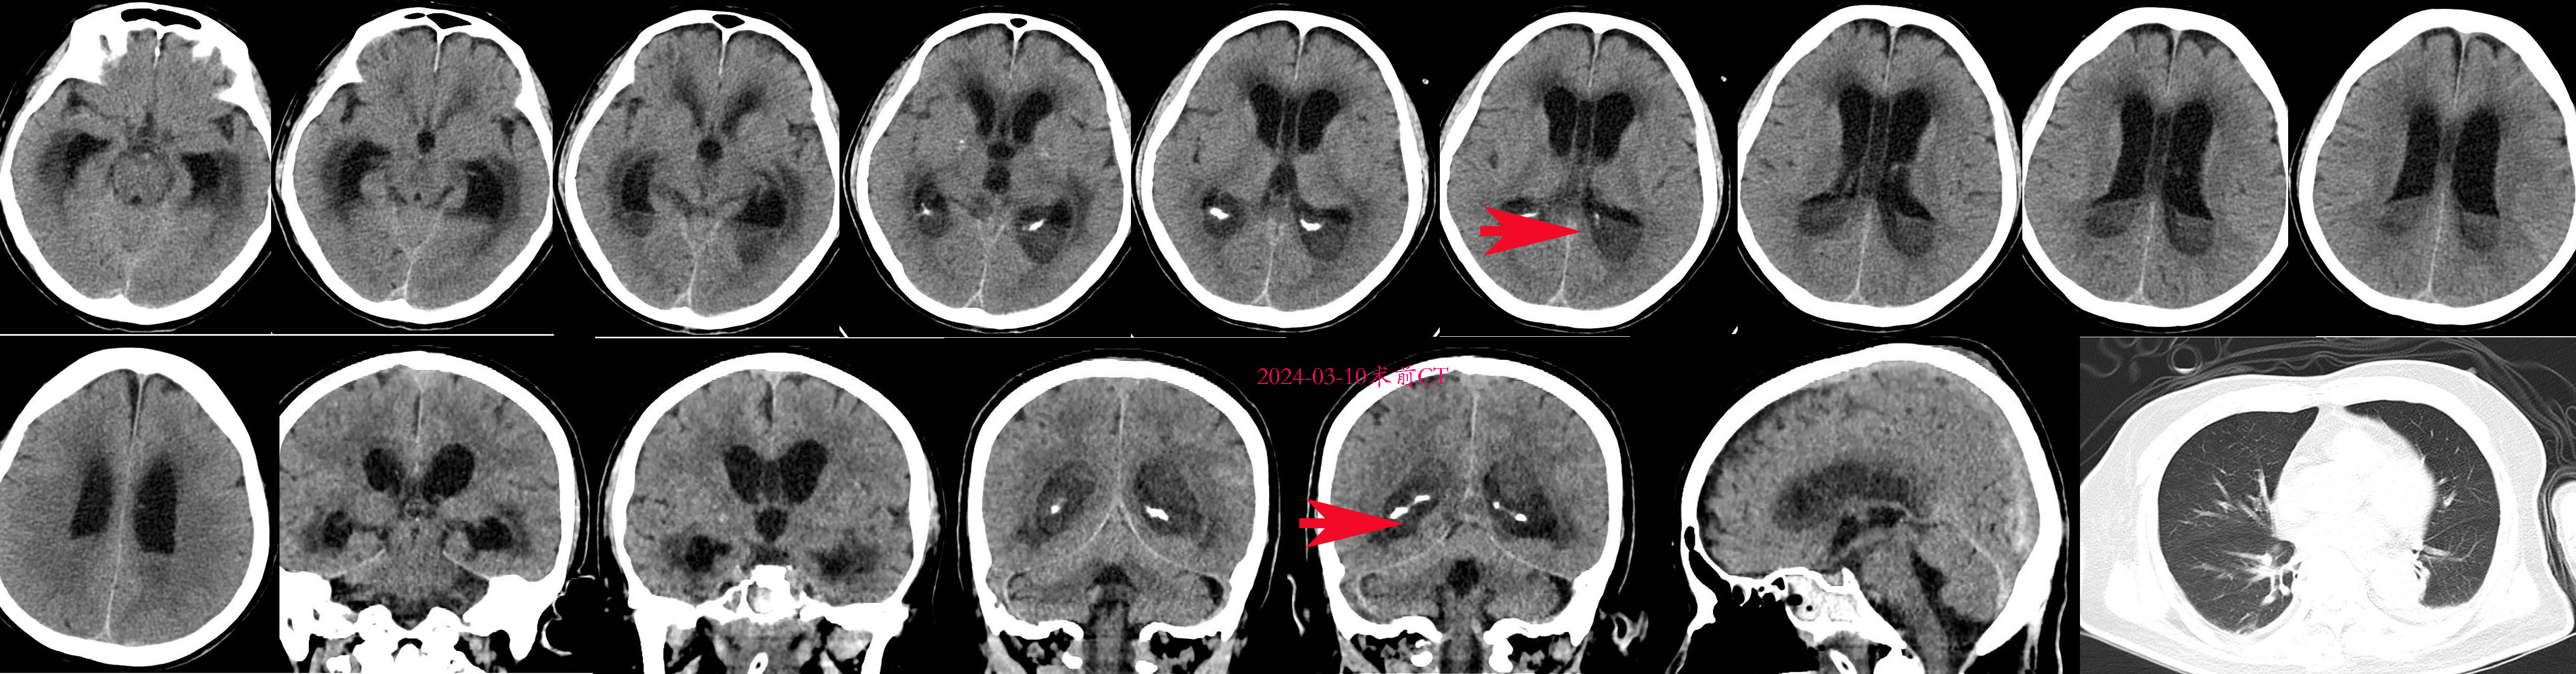

2024-03-10出现双侧瞳孔散大,直径4.5mm,但神志反应较前好转,刺痛睁眼,刺痛定位。呼吸机通气,升压药已停 。复查CT可见脑室扩大,脑积水,脑室内液平更明显(见下图红色箭头) 急诊全麻下行右额开颅脑内脓肿清除术+三脑室底造瘘术+侧脑室透明隔造瘘术+脑室钻孔外引流术。

急诊全麻下行右额开颅脑内脓肿清除术+三脑室底造瘘术+侧脑室透明隔造瘘术+脑室钻孔外引流术。

右侧脑室及枕角脓肿内镜下清除术

透明隔造瘘后进入左侧脑室及枕角内镜下脓肿清除